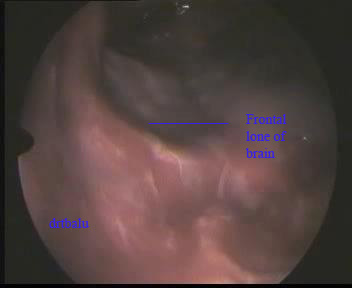

Using a 4mm 0° nasal endoscope the surgery was performed. The complete surgery was performed under general anesthesia. On deroofing the agger nasi cell the contents of the mucocele started to extrude. The frontal sinus ostium was widened. When the scope was introduced through the widened frontal ostium the posterior table of the frontal sinus was found to be eroded. The frontal lobe of the brain was clearly visible. The brain can be identified by its characteristic pulsations coinciding with the patient's respiration.

Endoscopic view of exposed brain tissue